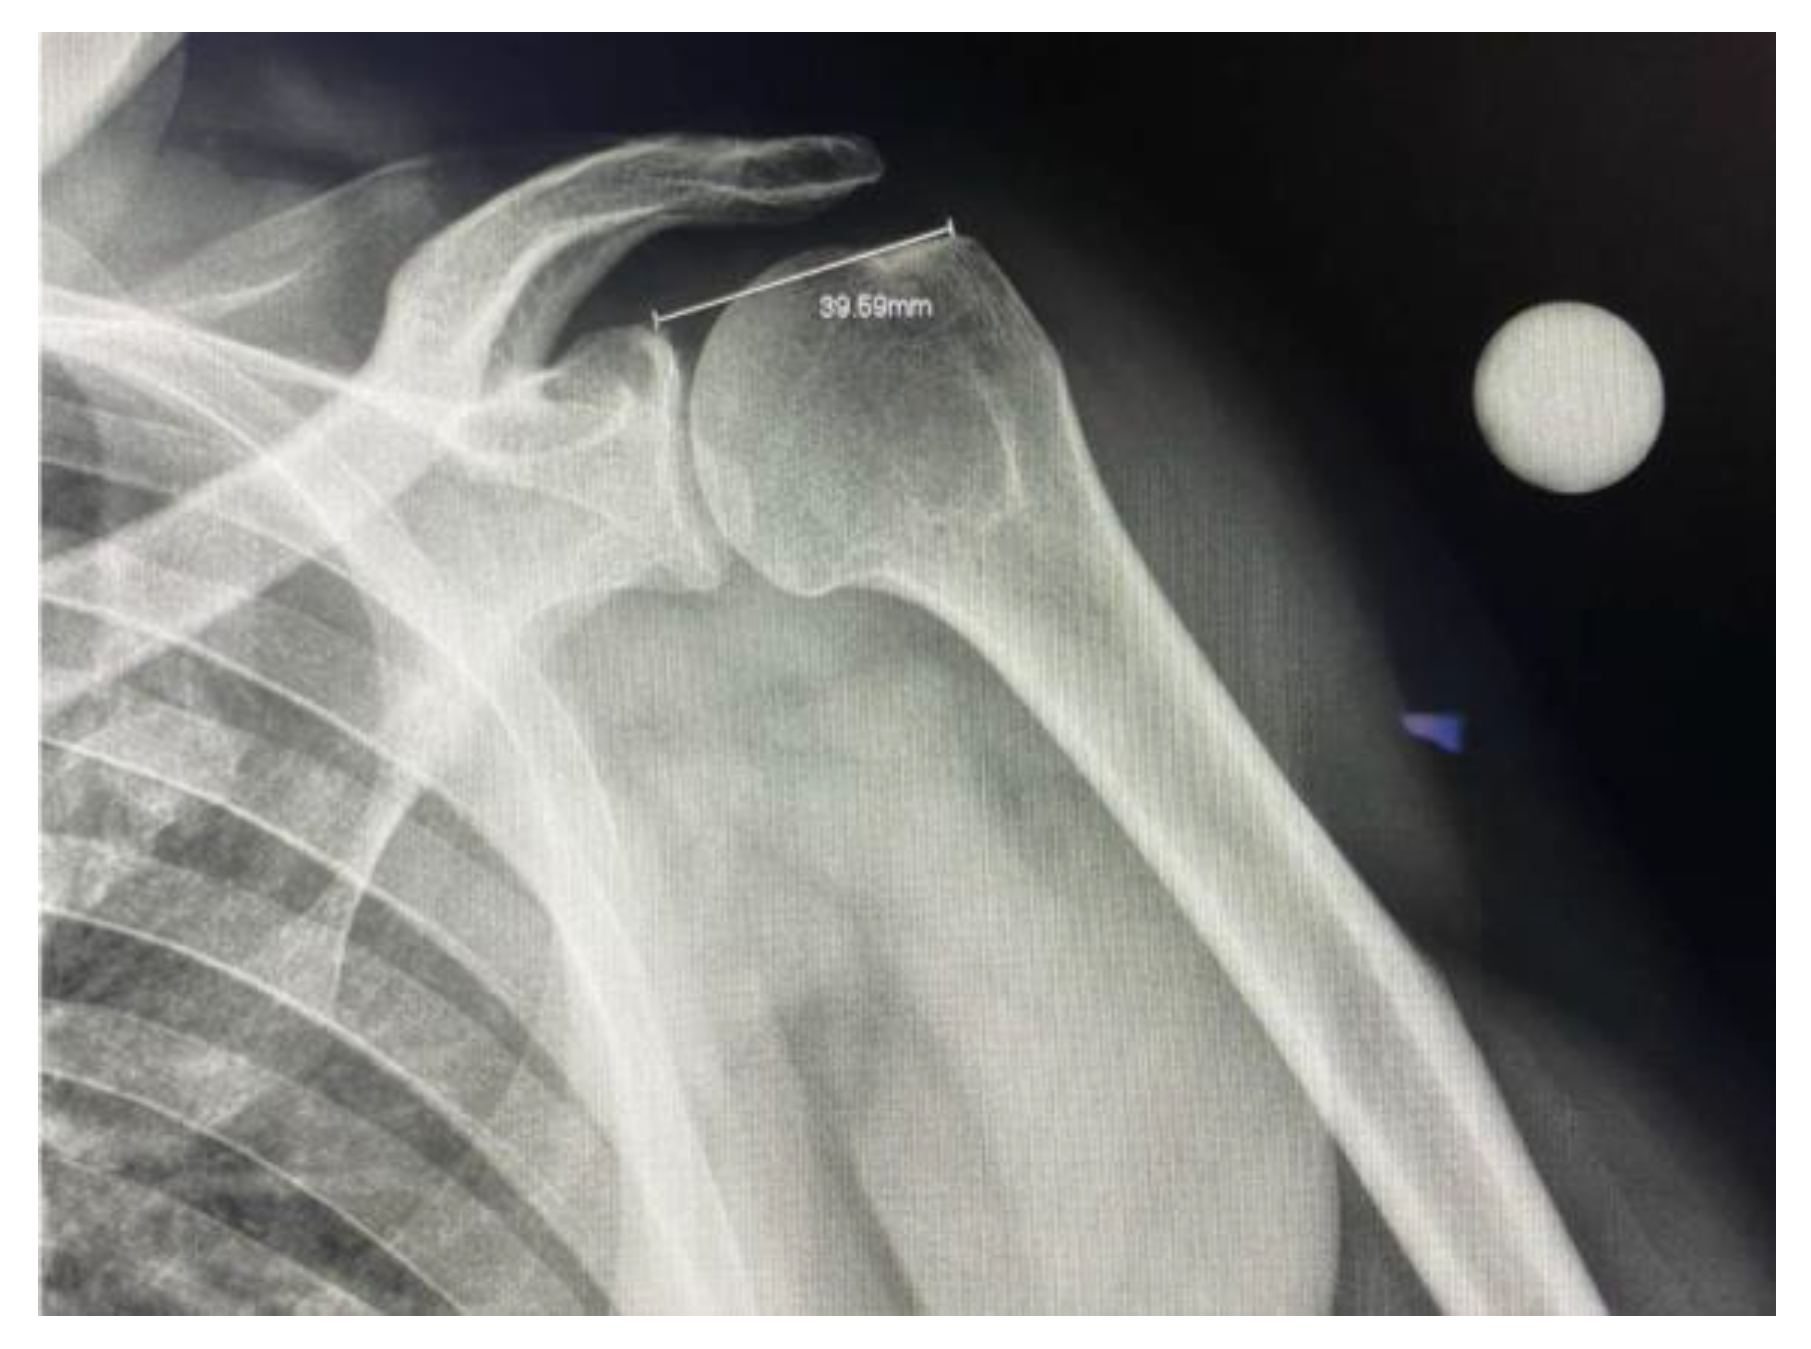

Figure 2. Plain film radiograph of the glenohumeral joint with a measurement of the distance between the superior glenoid and the insertion point of supraspinatus.

To ensure standardization, the X-ray tube was positioned at 20° caudal angulation centered at the glenohumeral joint. The superior glenoid and greater tuberosity were used as reference landmarks for measurement and quality of the image. A radiographic reference ball was placed at the level of the coracoid process, in contact with the subject’s skin.

After capturing the plain film radiograph, the raters were instructed to calibrate the system using the radiographic reference ball. Using the calibration measurement tool, a straight line was drawn through the diameter of the ball, and a real length value of 25 mm was entered manually. Upon calibration, the ruler device was used to place a marker at the superior aspect of the glenoid where the medial anchors would be placed and another at the greater tuberosity where the lateral anchors would be placed. The distance would then be generated. (Figure 2).